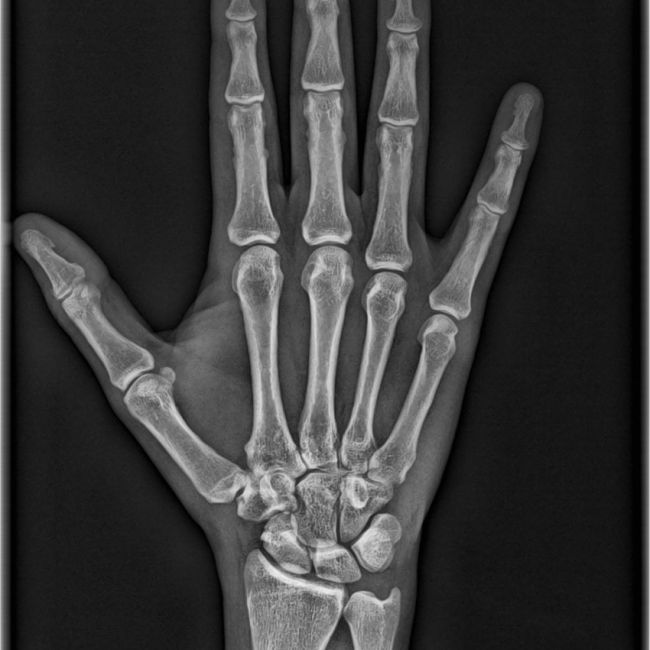

En los centros de Imagen Diagnóstica Dental Dr. Mayor ofrecemos una amplia variedad de servicios, gracias a la moderna aparatología con las que contanmos. Las pruebas diagnósticas que realizamos en nuestro centro son las siguientes: